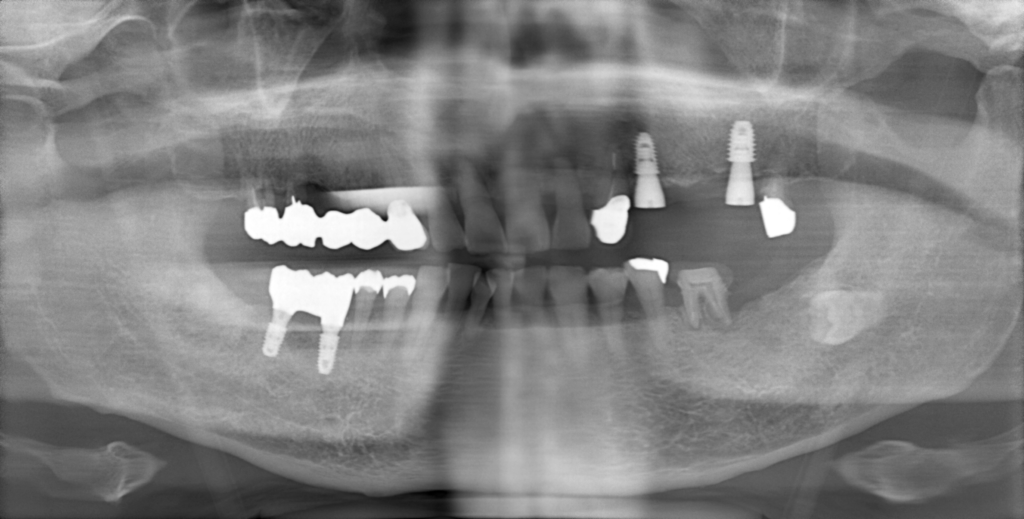

Y様インプラント実例 #44

左の上下の奥歯をインプラントで治療しています。

左下の奥歯は歯を抜くのと同時にインプラントの埋め込みを行っています。

被せものは上下、セラミックスで作っています。

治療前

治療後